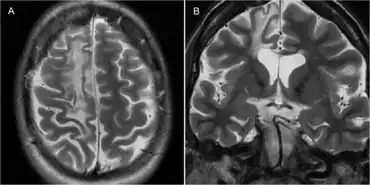

| Rasmussen encephalitis resulting in atrophy of the right frontal lobe as seen on MRI.[1] | |

The diagnosis may be made based on the symptoms alone, after ruling out other possible causes. An EEG will usually show the electrical features of epilepsy and slowing of brain activity in the affected hemisphere, and MRI brain scans will show gradual shrinkage of the affected hemisphere with signs of inflammation or scarring.[14]